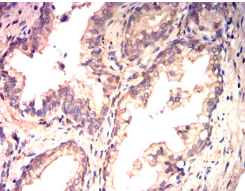

IHC    1/200 - 1/1000